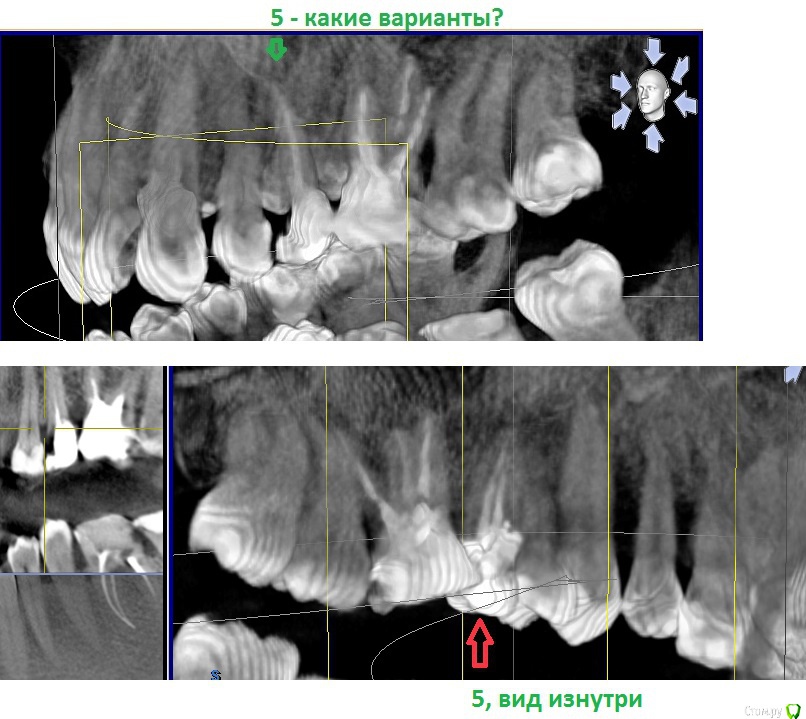

st_ Опубликовано 5 июня, 2018 Поделиться Опубликовано 5 июня, 2018 Добрый день.Проблема с верхней 5ркой. Забивается пища между 4 и 5 зубом.Хотел кардинально решить проблему - литой вкладкой в канал и коронкой, но протезист сказала, что в данном случае это невозможно. восстанавливай, мол, пломбой на штифте.какие вообще есть варианты? Ссылка на комментарий

Доктор Добрых Дел Опубликовано 5 июня, 2018 Поделиться Опубликовано 5 июня, 2018 Самый адекватный вариант это удаление 5,6зубов с последующей имплантацией 2 Ссылка на комментарий